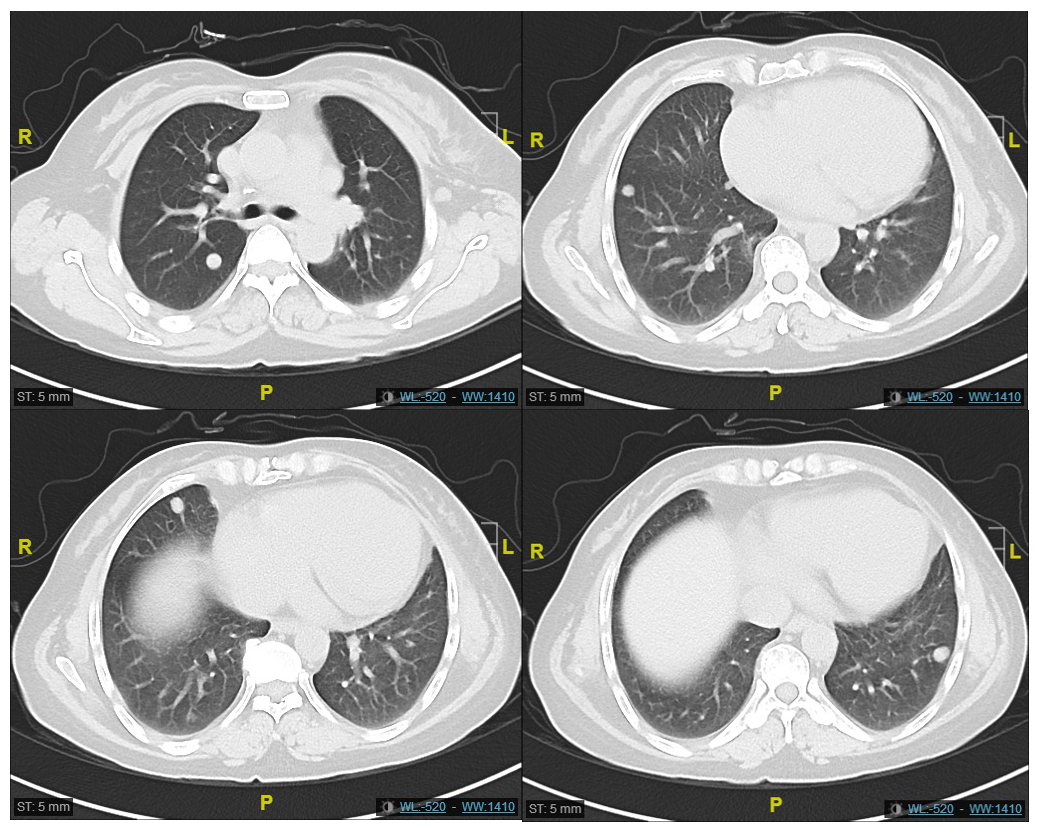

非小细胞肺癌(NSCLC)占肺癌的80~85%,超过一半的患者确诊时已为晚期。40%的亚洲患者存在表皮生长因子受体(EGFR)基因突变,90%的突变为EGFR 1...

肺癌是我国最常见的恶性肿瘤,10%~15%的非小细胞肺癌(NSCLC)患者在初诊时已发生脑转移,在整个疾病病程中约50%的患者会发生脑转移。靶向药物以及免疫疗法的...